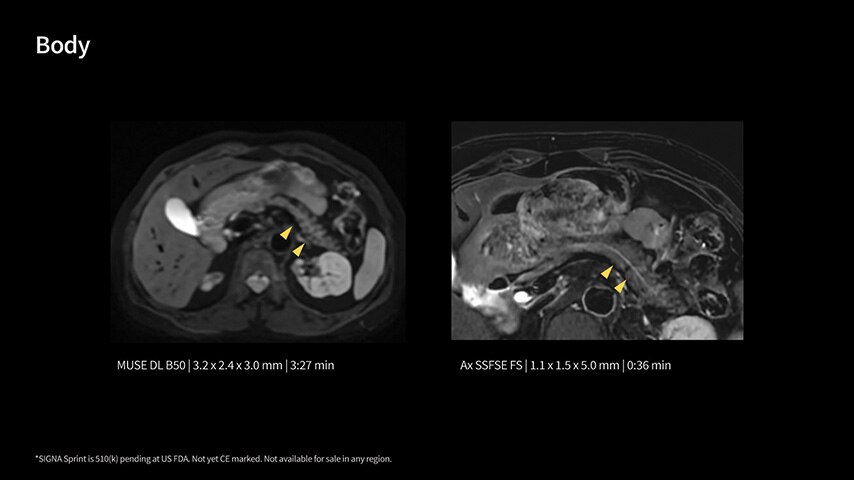

In oncological assessments, diffusion imaging is a critical clinical indicator. SIGNA Sprint offers clearer diffusion, reduced distortion, and improved SNR.¹

Within cardiovascular diseases, the functional assessment of the heart is an essential imaging application. SIGNA Sprint is powered by built-in AI technologies—Sonic DL™, AIR Recon DL and AIR x™—enabling high-quality imaging even in the most demanding anatomies.

Imaging capabilities to unlock the power to explore further

High gradient performance

The growing clinical need within oncology and cardiology requires an MRI scanner that can rise to the challenge. With a high gradient performance of 65/200, SIGNA Sprint helps deliver crystal-clear imaging for ultimate diagnostic confidence. Improved signal-to-noise ratio (SNR) and diffusion, with deep-learning solutions that could enhance diagnostics and treatment response monitoring in your oncology patients.¹ Additionally, the shift from qualitative to quantitative cardiac MRI reduces the time and expertise needed to interpret scans and offers greater consistency and reliability. Helping you to unlock the power to explore further - even in your most challenging cases.